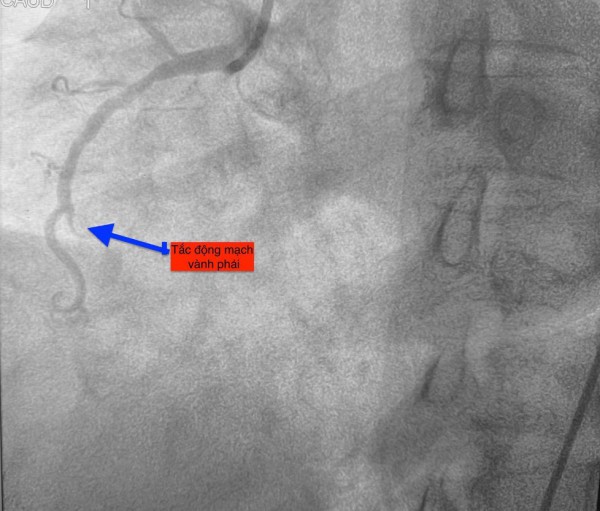

Trường hợp thứ nhất, lúc 0 giờ 34 phút ngày 14.11, nam bệnh nhân 51 tuổi vào bệnh viện vì mệt và khó thở. Chụp mạch vành phát hiện bệnh nhân bị tắc hoàn toàn động mạch vành phải.

Trường hợp thứ hai, lúc 9 giờ 5 phút, nam bệnh nhân 53 tuổi nhập viện vì chóng mặt và nóng rát thượng vị. Điện tâm đồ ghi nhận nhồi máu cơ tim cấp vùng dưới. Kết quả chụp mạch vành xác định bệnh nhân cũng bị tắc động mạch vành phải.

Trường hợp thứ ba, lúc 15 giờ 53 phút, nam bệnh nhân 78 tuổi nhập viện vì đau ngực. Bệnh nhân cho biết đau ngực từng cơn trong 3 ngày, ngày nhập viện thì đau ngực liên tục. Điện tim gợi ý nhồi máu cơ tim cấp; chụp mạch vành cấp cứu phát hiện bệnh nhân cũng tắc động mạch vành phải.

Hình ảnh chụp mạch vành cho thấy các bệnh nhân bị tắc mạch máu tim (do mảng xơ vữa, huyết khối) dẫn đến tình trạng thiếu máu cục bộ và nhồi máu cơ tim cấp

ẢNH: BV